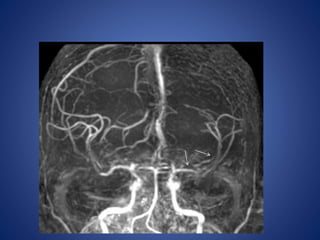

5 yrs male child with history of left sided focal seizures with secondary generalization

5 yrs malechild with history of left sided focal seizures with secondary generalization

• Stenosis/occlusion ofthe distal ICA • moyamoya vessels with signal voids in the basal ganglia • ischemia • infarction • atrophy, and ventriculomegaly. • Small abnormal net-like vessels proliferate giving "puff of smoke" appearance. • Contrast-enhanced T1WI - marked leptomeningeal enhancement along the cortical sulci (ivy sign). often show contrast stagnating in slow-flowing collateral vessels both in the brain parenchymal and over its surface. MR imaging